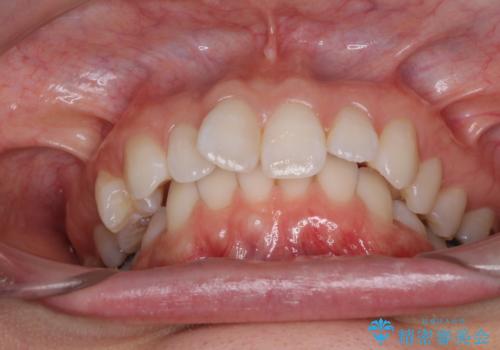

深い咬み合わせと奥歯のむし歯 総合歯科治療

- 奥歯の虫歯と前歯のデコボコや突出感を気にして来院された患者様です。

上顎歯列が、下顎に対して前方にありましたが、口元に出っ歯の印象がなかったため、親知らずを抜歯した上で、上顎歯列全体を後方に移動させることとしました。

咬合力が強いため、アンカースクリューを使用し、ワイヤー装置にて矯正治療を行うこととしました。